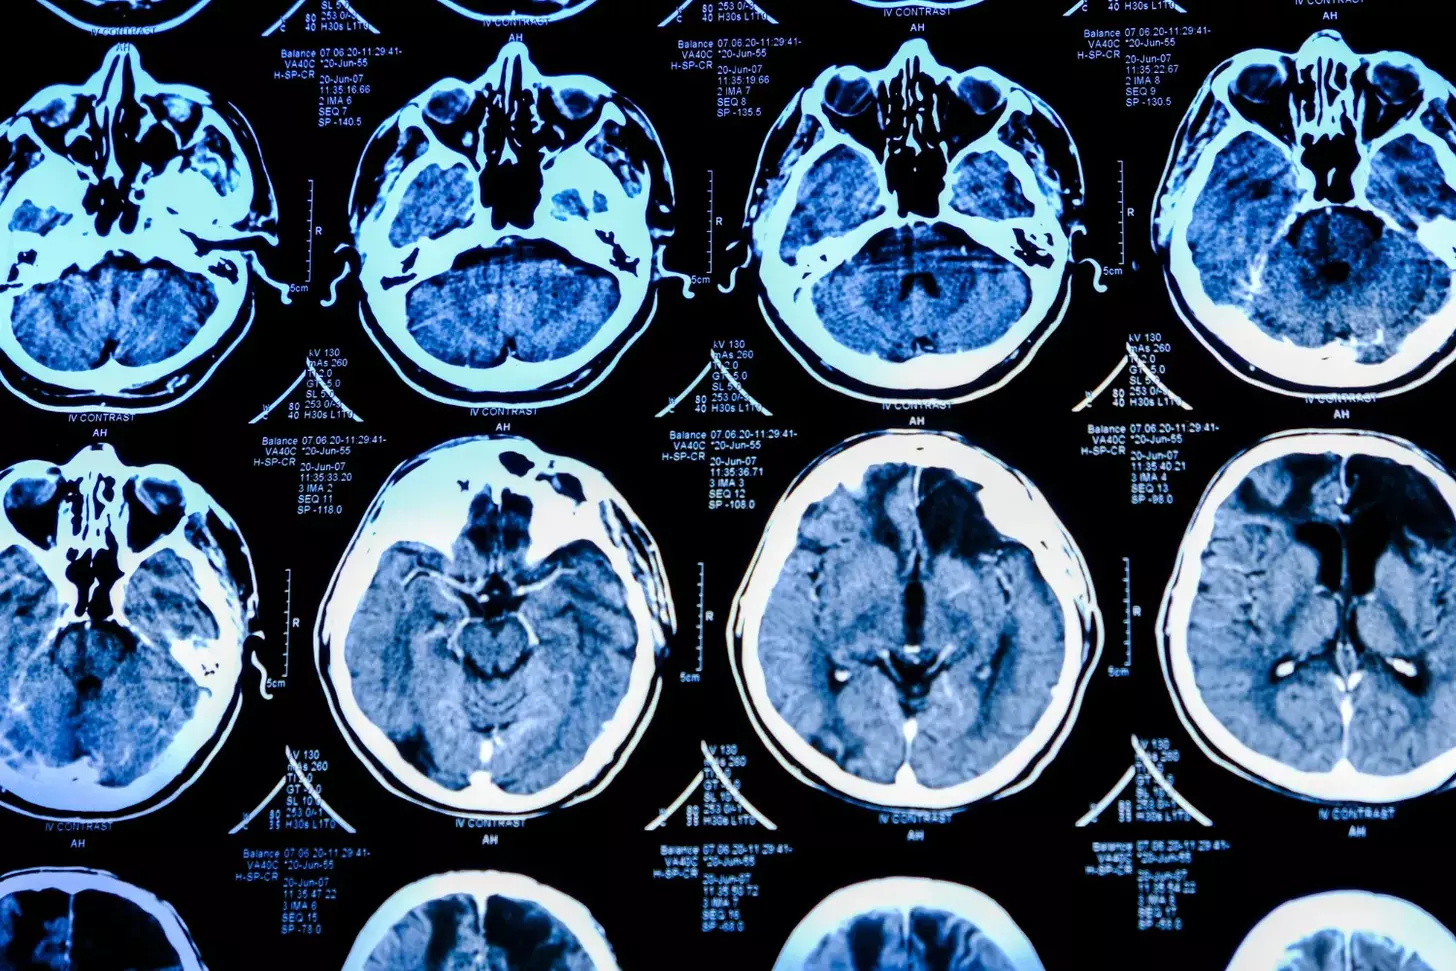

Advanced imaging is key in diagnosing and staging brain tumors. We use different imaging methods to see the tumor and its area.

Magnetic Resonance Imaging (MRI) is a top choice for brain tumors. It gives detailed brain images. This helps us see the tumor’s size, location, and details.

Computed Tomography (CT) scans are used too, mainly in emergencies or when MRI is not available. CT scans show the tumor’s structure and its effect on brain tissue.

Advanced imaging techniques like MRI and CT scans are vital in brain tumor staging. They help determine the tumor’s characteristics, location, and extent. This information guides treatment decisions.